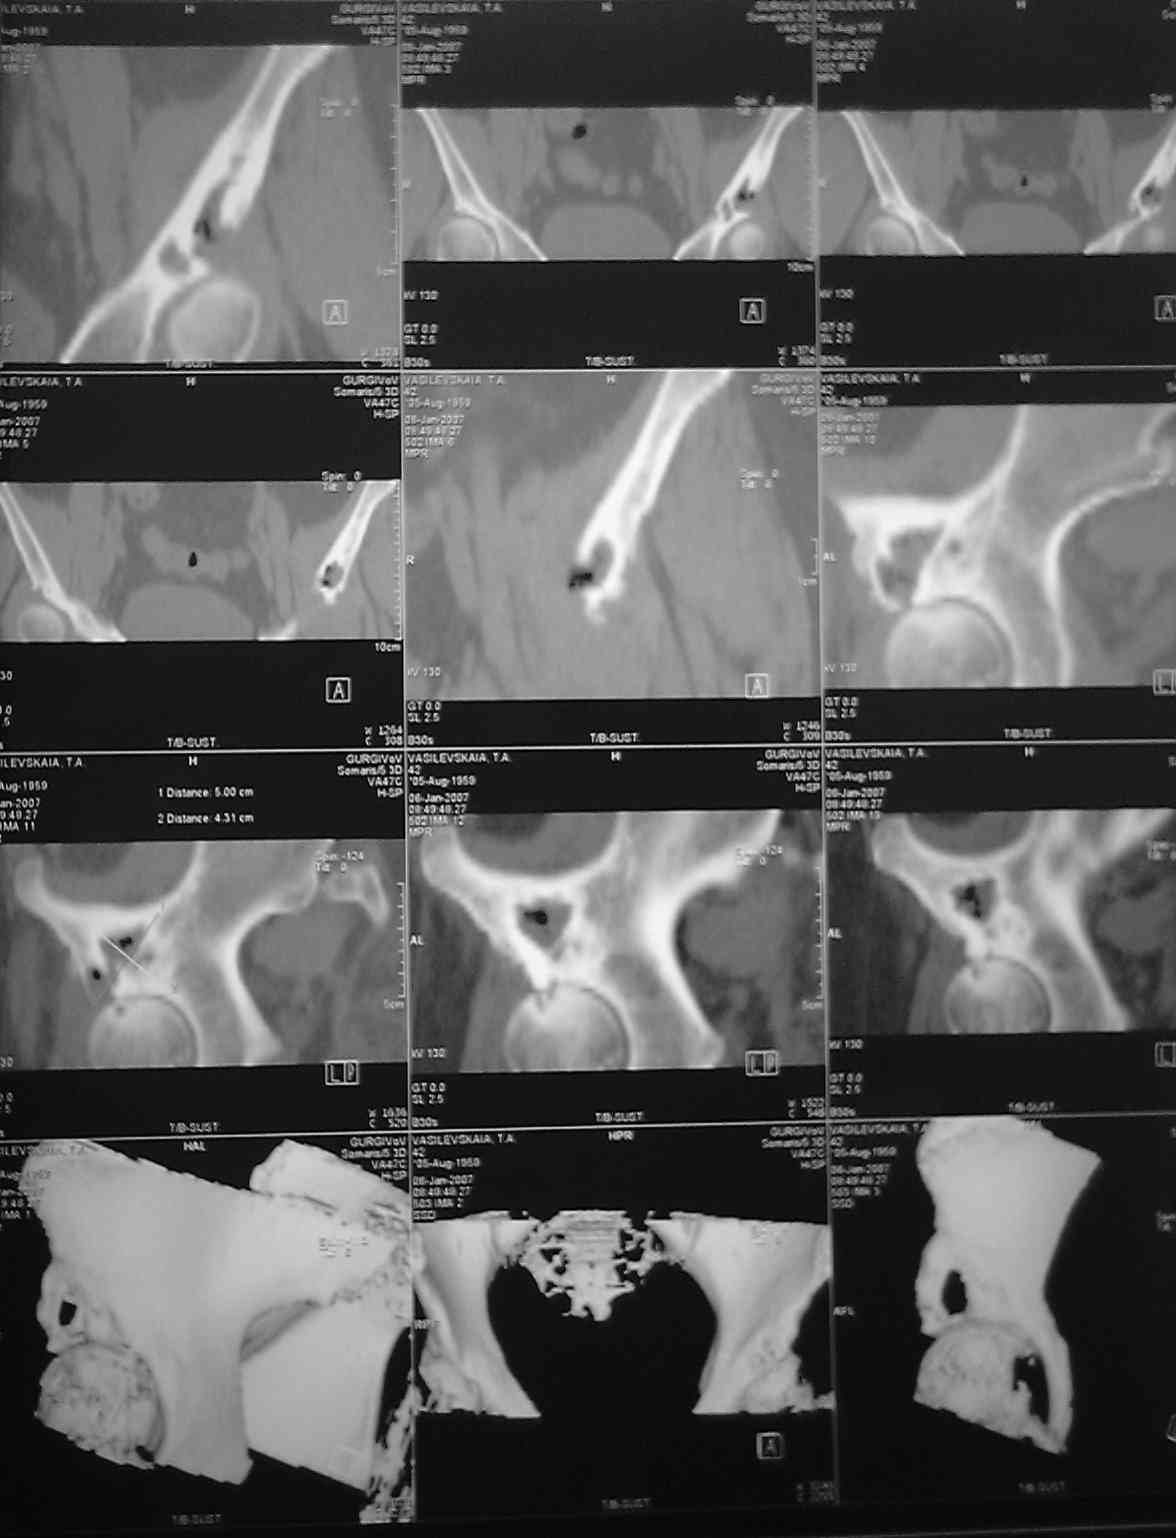

нвообразование седалищной кости |

Коллеги .пожалуйста помогите. Представляю КТ нашей операционной сестры.Боли в тазобедренном суставе беспокоят около 2-х лет.В последние2-3 месяца

боли усилились, хотя интесивность была умеренная. Продолжала работать проводя,в операционные дни, стоя, по 7-8 часов.Рентгенологом (очень предположительно) выставлен диагноз-туберкулез. Я даже предположительно затрудняюсь поставить диагноз, но, по-видимому, без операции с экспресс-биопсией не обойтись, иначе исход в патологический перелом с центральным вывихом. Три вопроса: 1)Что это? 2)Где лечится? 3)цена вторго вопроса? Больная - гражданка РФ и жена старшего офицера запаса, так что право на лечение в госпиталях МОРФ вроде бы имеет. Но мед. страховки нет. У нас ее просто не выдавали. Заранее благодарен, как я, так и коллектив хирургического отделения.(госпиталь МО г.Тирасполь)